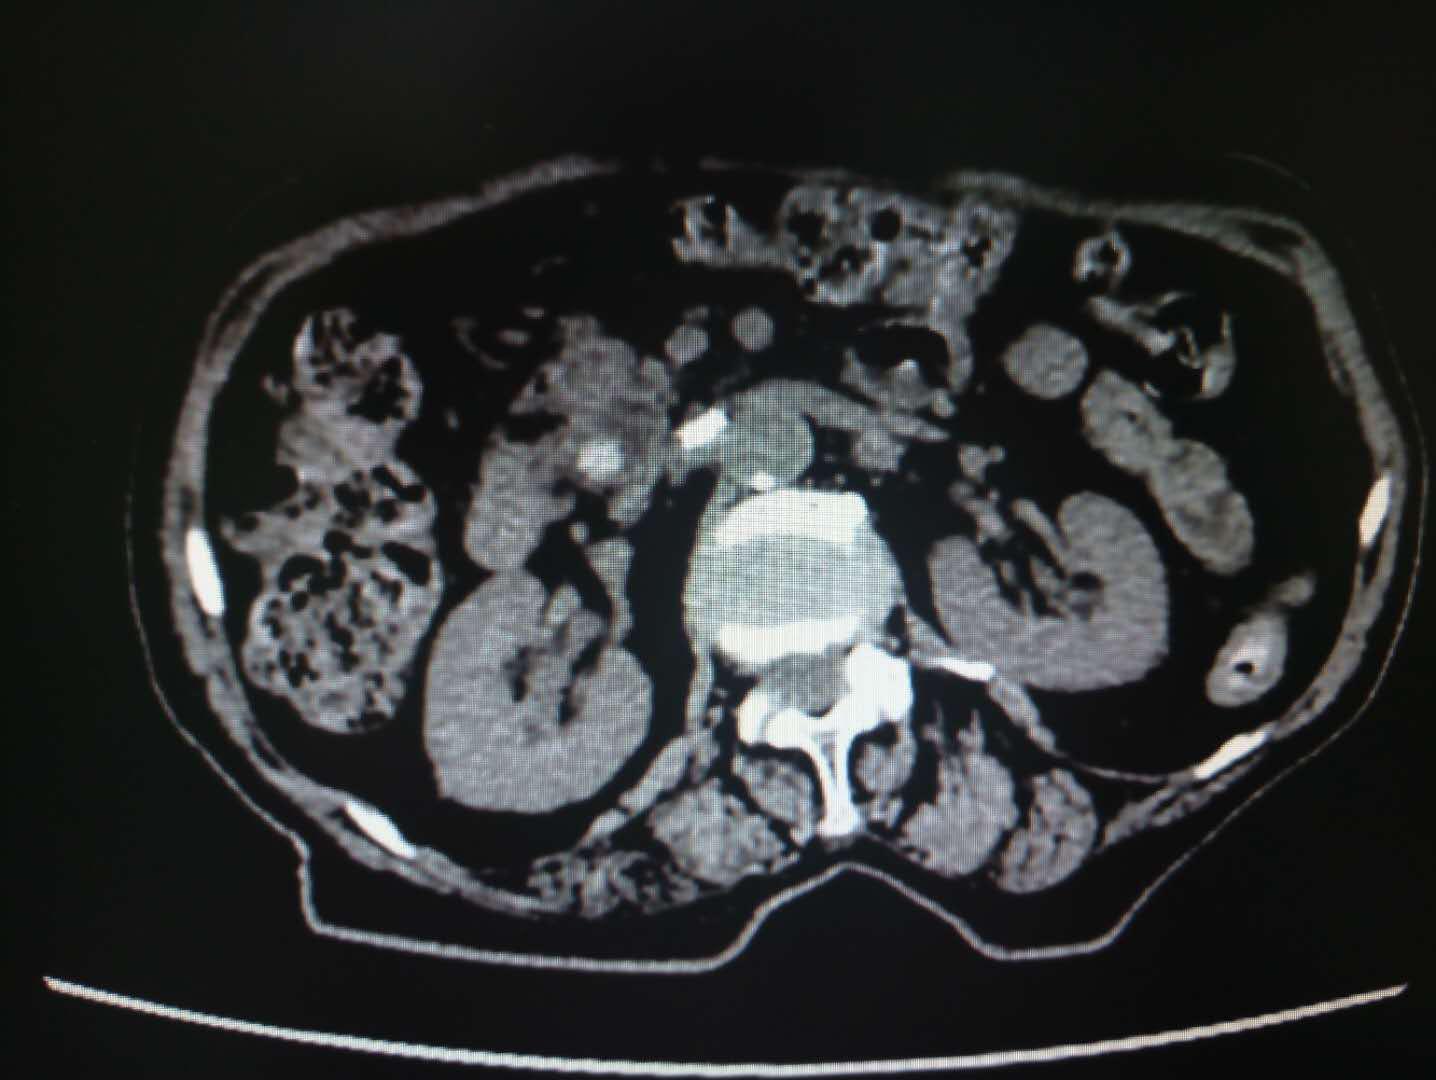

患者梁某,女性,87岁,因“腹痛2月”收住消化内科,诊断为胆总管结石、化脓性胆管炎、冠心病、心房纤颤、高血压2级、脑梗塞、电解质紊乱(低钾血症)。患者入院后伴有发热,最高体温41℃,急性化脓性胆管炎症状急剧加重,生命危在旦夕,一分一秒都在与生命赛跑。以往唯一生还的机会就是开刀手术,但是这位高龄患者很难下手术台;如果保守治疗唯一的结果就是因感染性休克及严重合并症而死亡。就在此时,消化内科主任王宇晖、主治医师曹鹏、白欣与手麻科雷育华主治医师、介入科何彤副主任多学科联合会诊,根据病情迅速制定了最佳手术方案,那就是为患者实行ERCP胆道取石。手麻科迅速为患者实行插管麻醉,密切监护生命体征,介入科配合,由曹鹏医生快速将胆管内的巨大结石顺利取出,迅速解除了胆道梗阻,缓解了患者胆道压力,安全有效缓解了患者的危重病情。